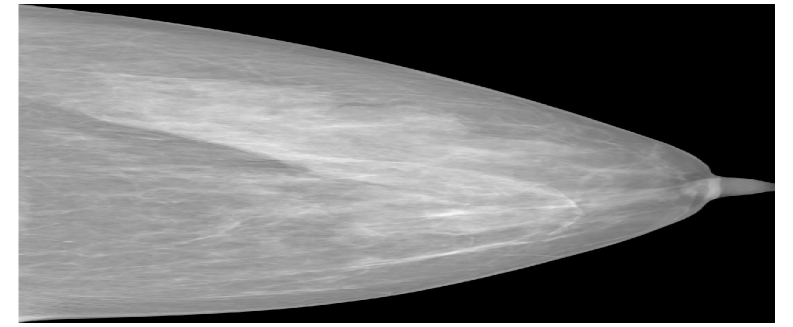

As data augmentation, random Gaussian noise (μ=0\mu=0, σ=0.005\sigma=0.005), random horizontal flipping (p=0.5p=0.5), random rotation (15-15^{\circ}, +15+15^{\circ}), random translation (0, 0.1), random shearing (25-25^{\circ}, +25+25^{\circ}), scaling by a random factor between 0.8 and 1.6 were used. Three standardized mammography images from different datasets are shown in the Figure 6.

Refer to caption

(a) Hacettepe

(b) VinDr

(c) CSAW

Figure 6: Standardized mammography samples from Hacettepe, VinDr, and CSAW dataset.